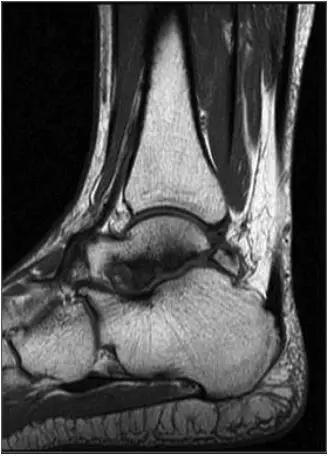

3、MR表现:

- 三角籽骨或距骨后三角结构模糊和变形,T1WI信号降低, T2WI信号升高,

- 周围脂肪水肿,

- 踇趾长屈肌腱信号升高,见鞘膜积液,

- 胫骨后下跟骨上缘骨结构形态变化和信号异常,

- 三角籽骨和距骨退行性囊变。

三角籽骨综合征

三角籽骨综合征并跟腱滑囊积液